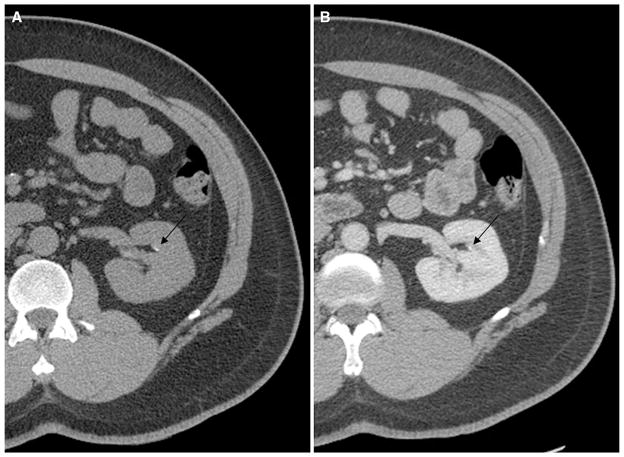

As manifested by the much lower sensitivities of the <2 and <3 mm stone categories, most of the undetected stones in our series were relatively small, with a mean diameter of 2.1 mm. However, many very small stones could still be detected on the contrast-enhanced images. Figure 3 provides an example of one such stone.

Fig. 3.

A 69-year-old man with microscopic hematuria. Noncontrast (A) and postcontrast (B) CT images demonstrate a 1.1-mm non-obstructing calyceal stone in the left kidney (arrows). This stone was detected on the postcontrast series of images by all three reviewers.